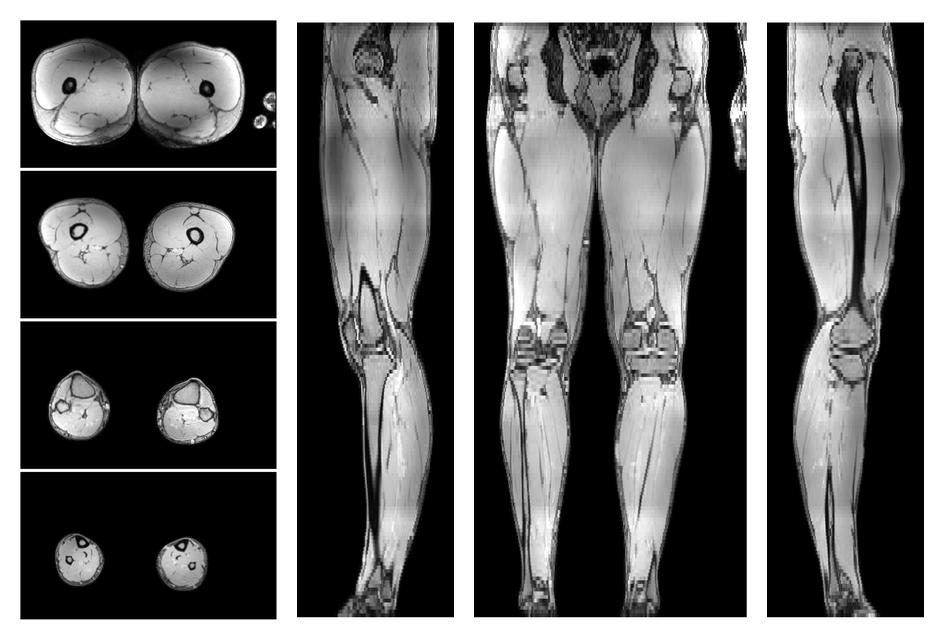

• Out phase image

The out-phase image of the dixon reconstruction for water fat quantification.